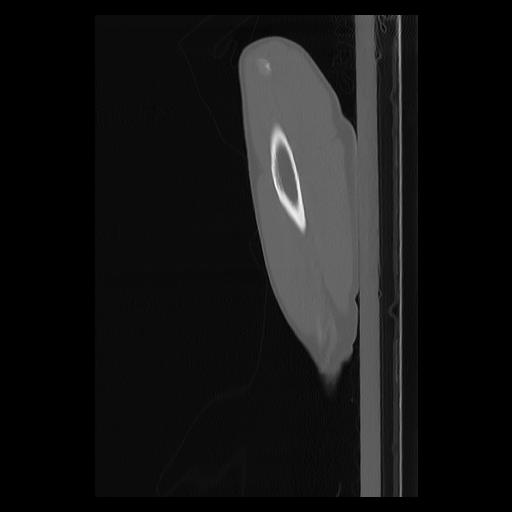

33 PULMON,CE,Sagittal,3.000,PULMON,Sagittal,